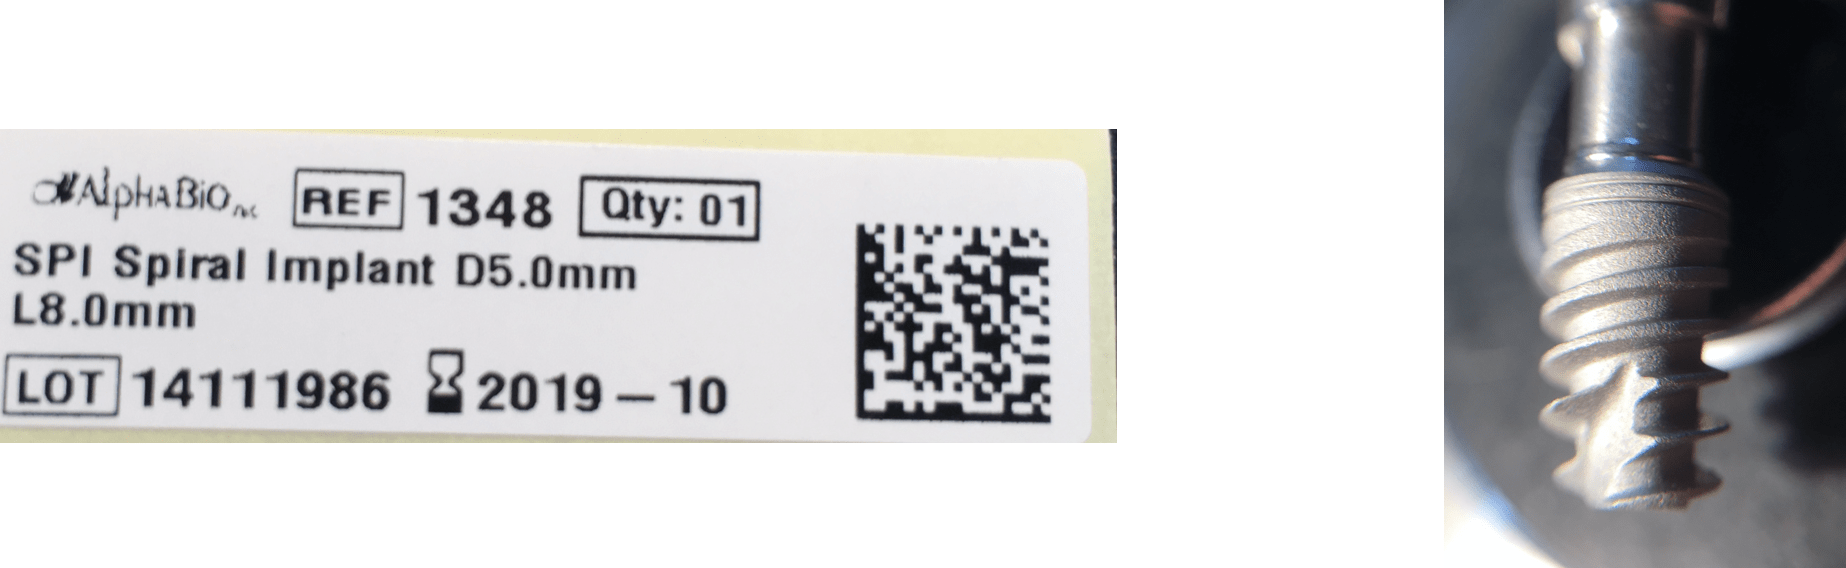

3 Alpha-Bio Tec - SPI Spiral Implant LOT 14111986

SPI Spiral Implant LOT 14111986 Exp.Date:2019-10